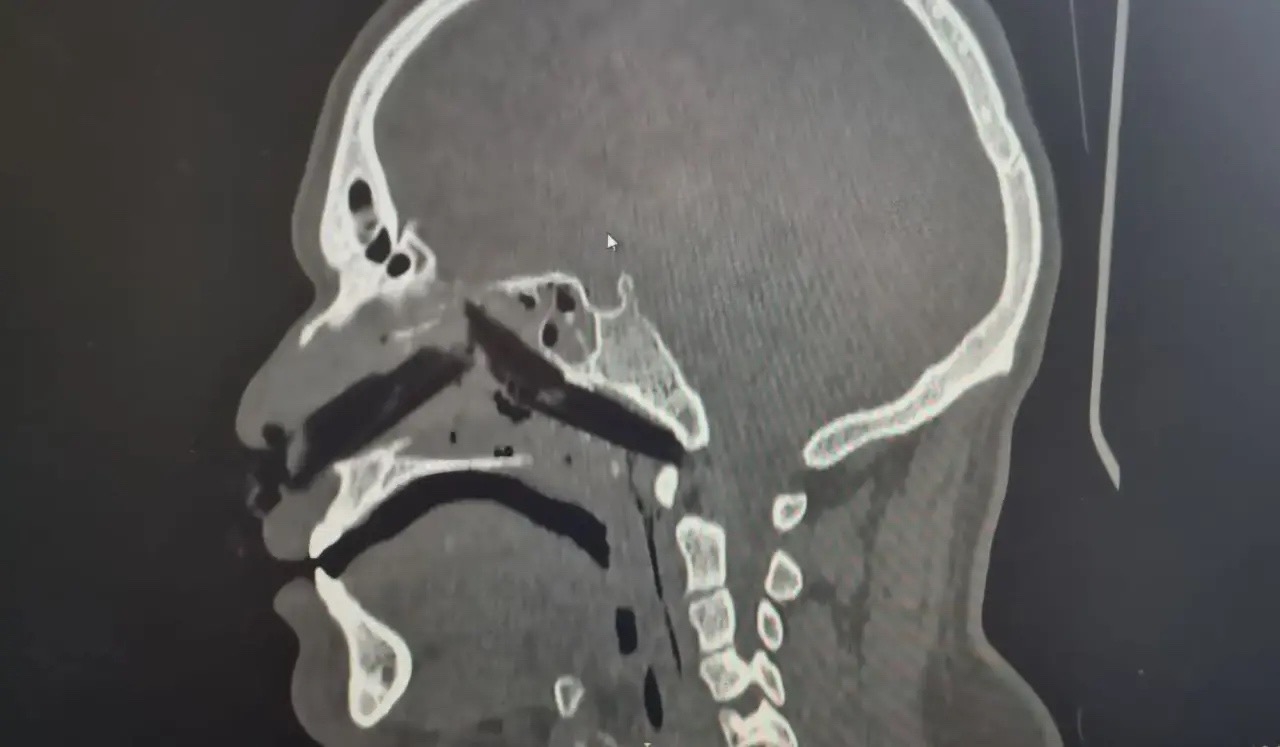

Команда оториноларингологов Вологодской областной клинической больницы провела успешную операцию по извлечению инородного тела из носовой полости пациента.

Тридцатилетний мужчина получил травму на производстве, в его носу оказалась деревянная щепка длиной более 10 сантиметров. Пострадавшего оперативно доставили в больницу, где хирурги провели операцию длительностью 1,5–2 часа.

Фото: Вологодская областная клиническая больница